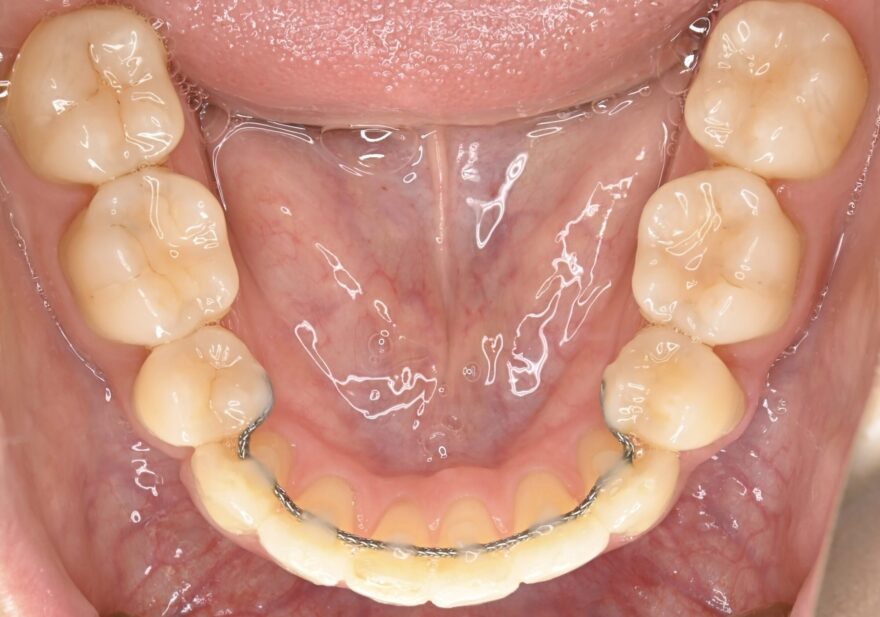

治療後の口腔内写真

約2年の動的期間(歯を動かす時期)で、ここまで美しい歯並びになりました。

ベーシックな表側矯正を選んで頂いても、最終的な仕上がりに差はありません。

前歯のガタガタが無くなりました。

前歯には後戻りを防止するための保定装置が装着されています。

下顎の前歯にもワイヤーによる保定装置を装着しました。